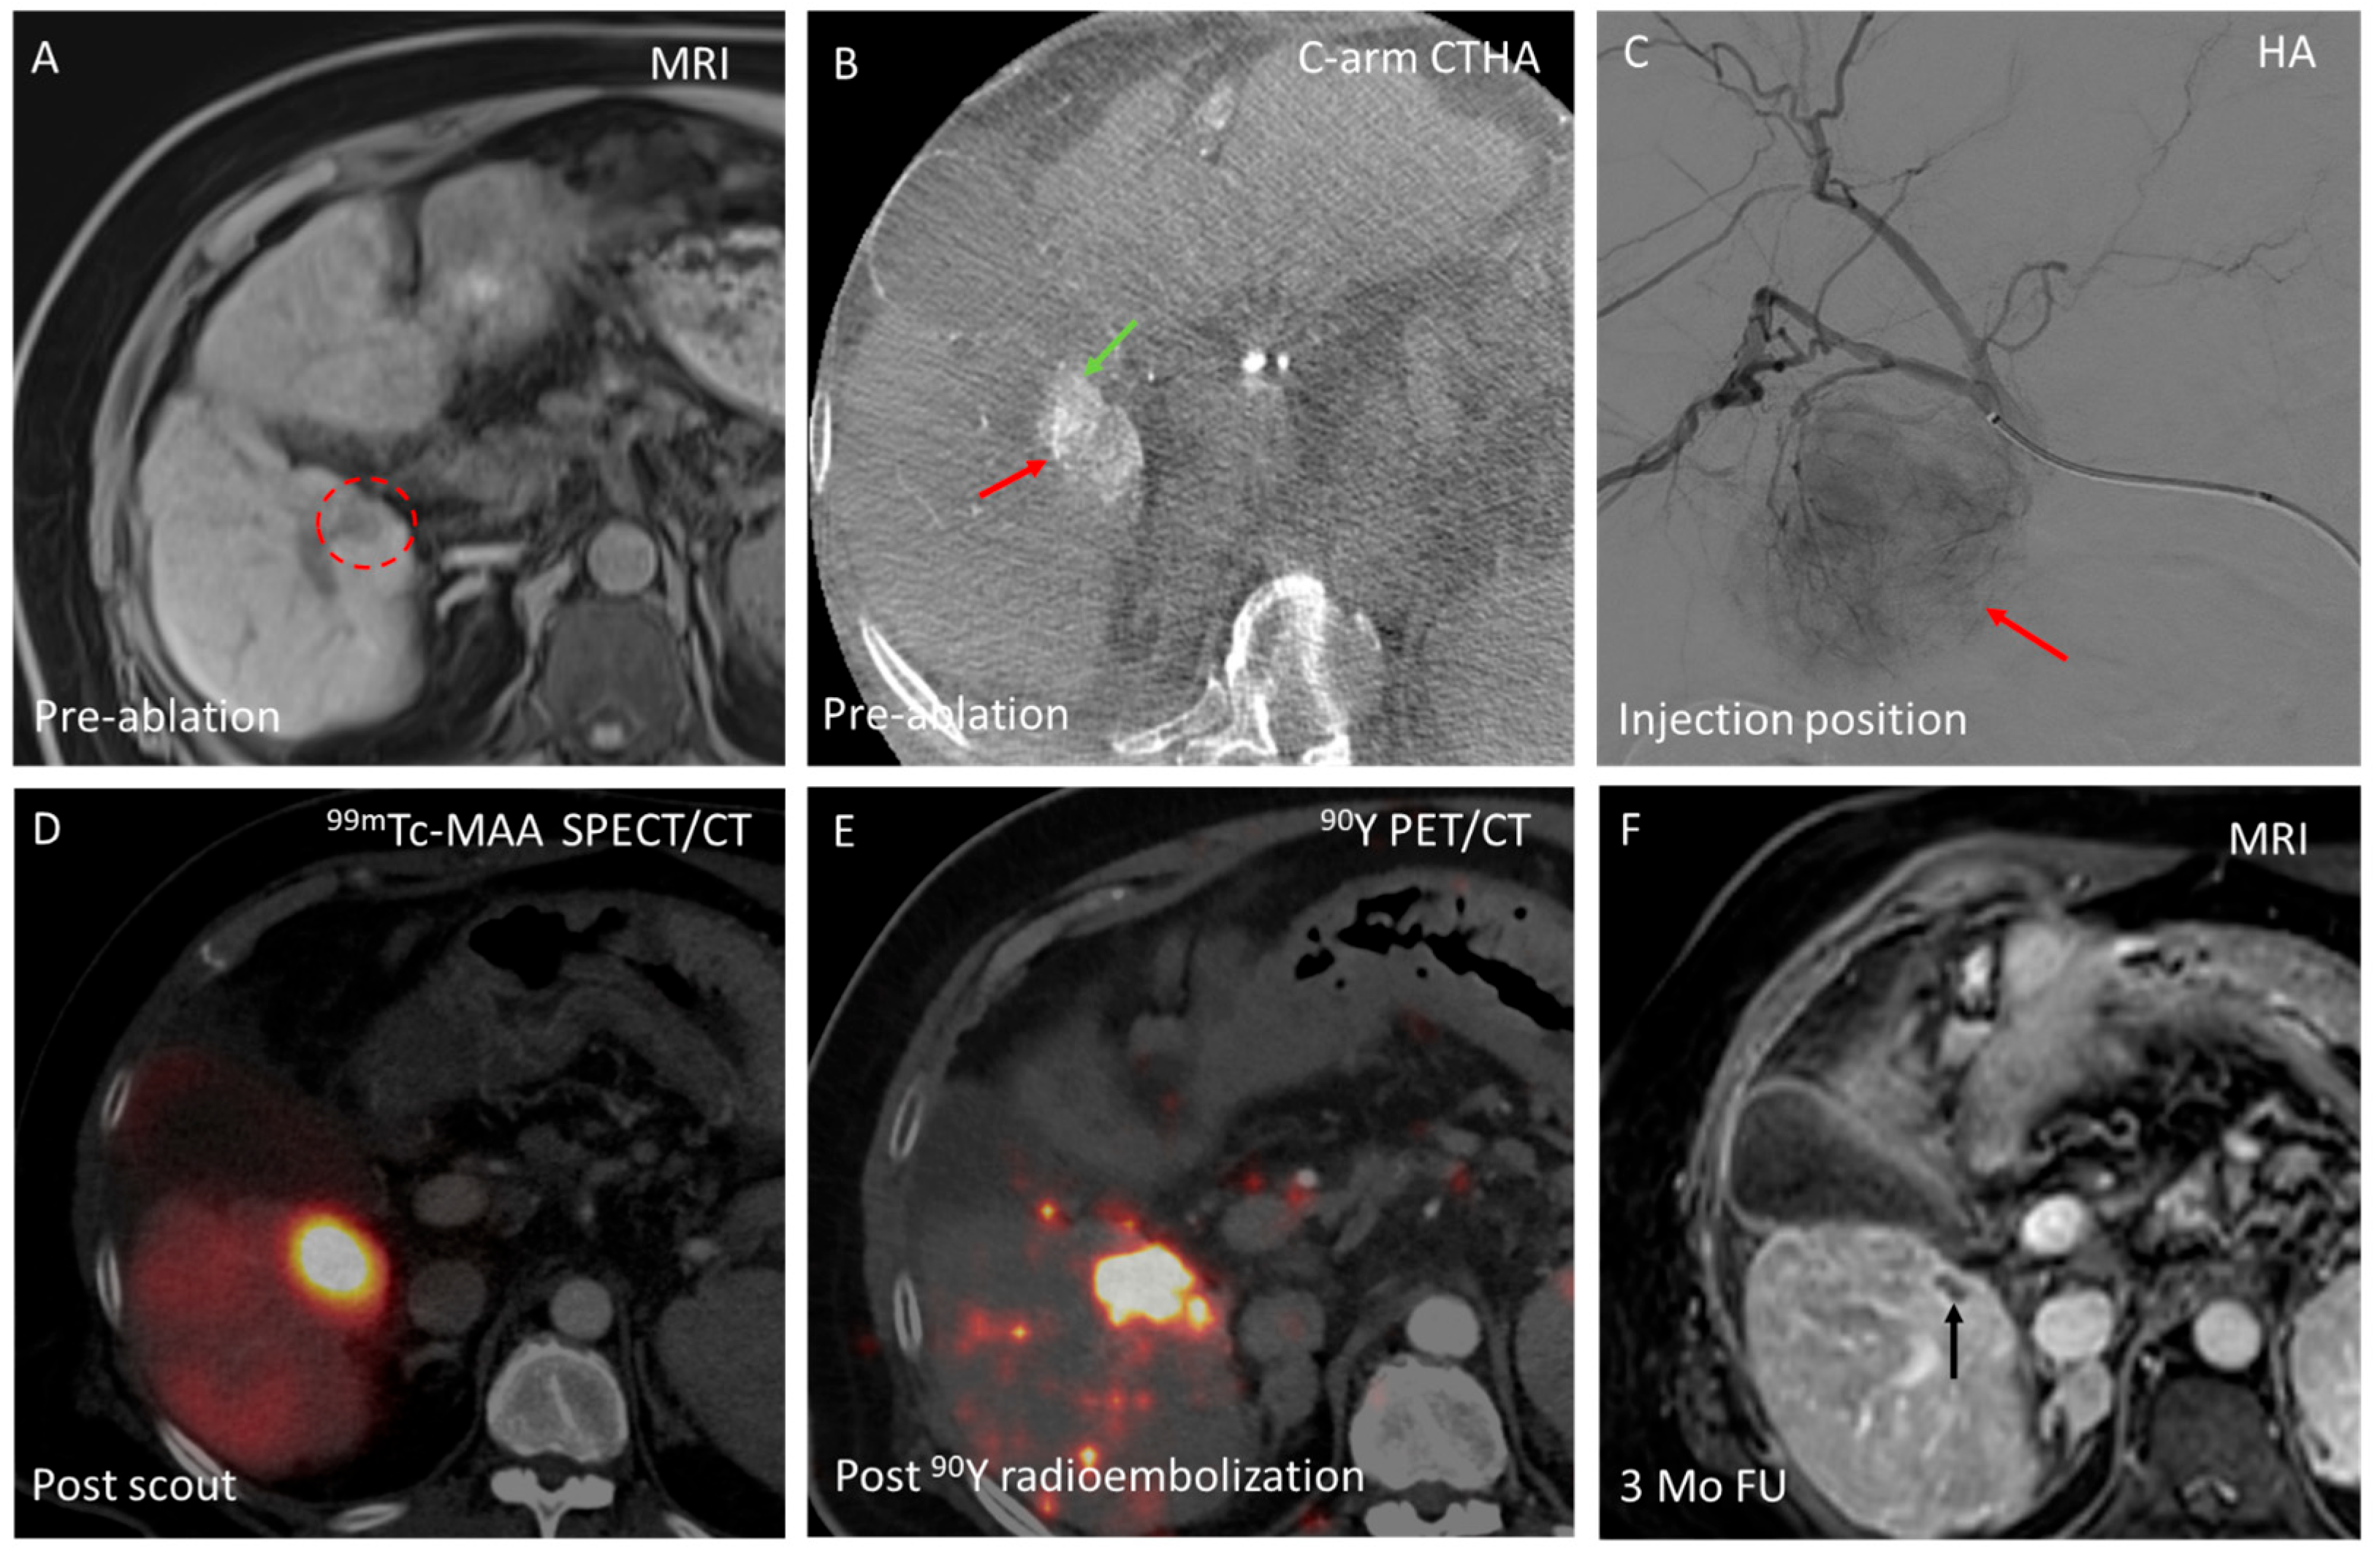

3.3. Domain C—Enhancing Ablation Effect